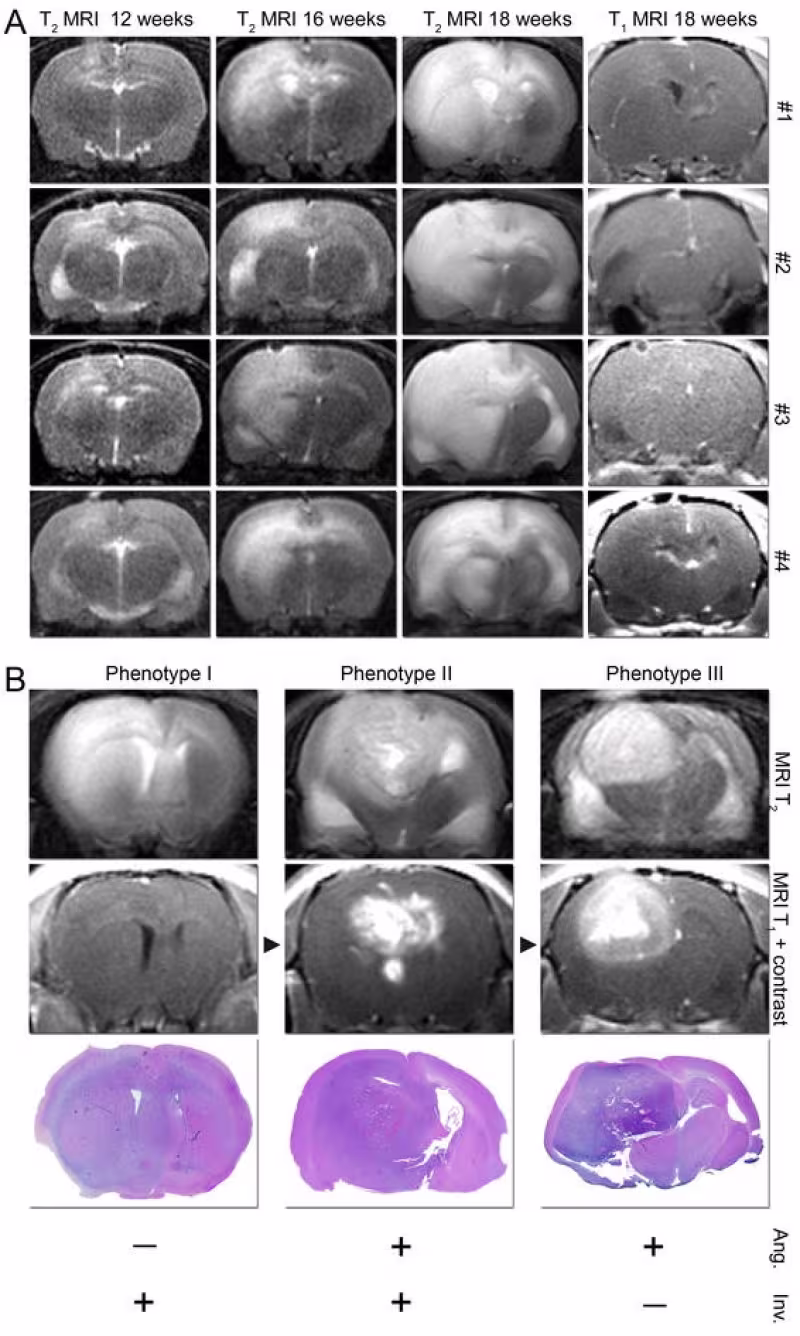

Brain tumours established from human biopsies. (A) MRI demonstrates highly reproducible growth in four rats (#1-4) grafted with tumor tissue from the same biopsy. MRI scanning at time points indicated. (B) MRI scans of 3 distinct phenotypes with different combinations of invasive and angiogenic growth. (C) Corresponding H/E tumour sections. Photo: Per Øyvind Enger